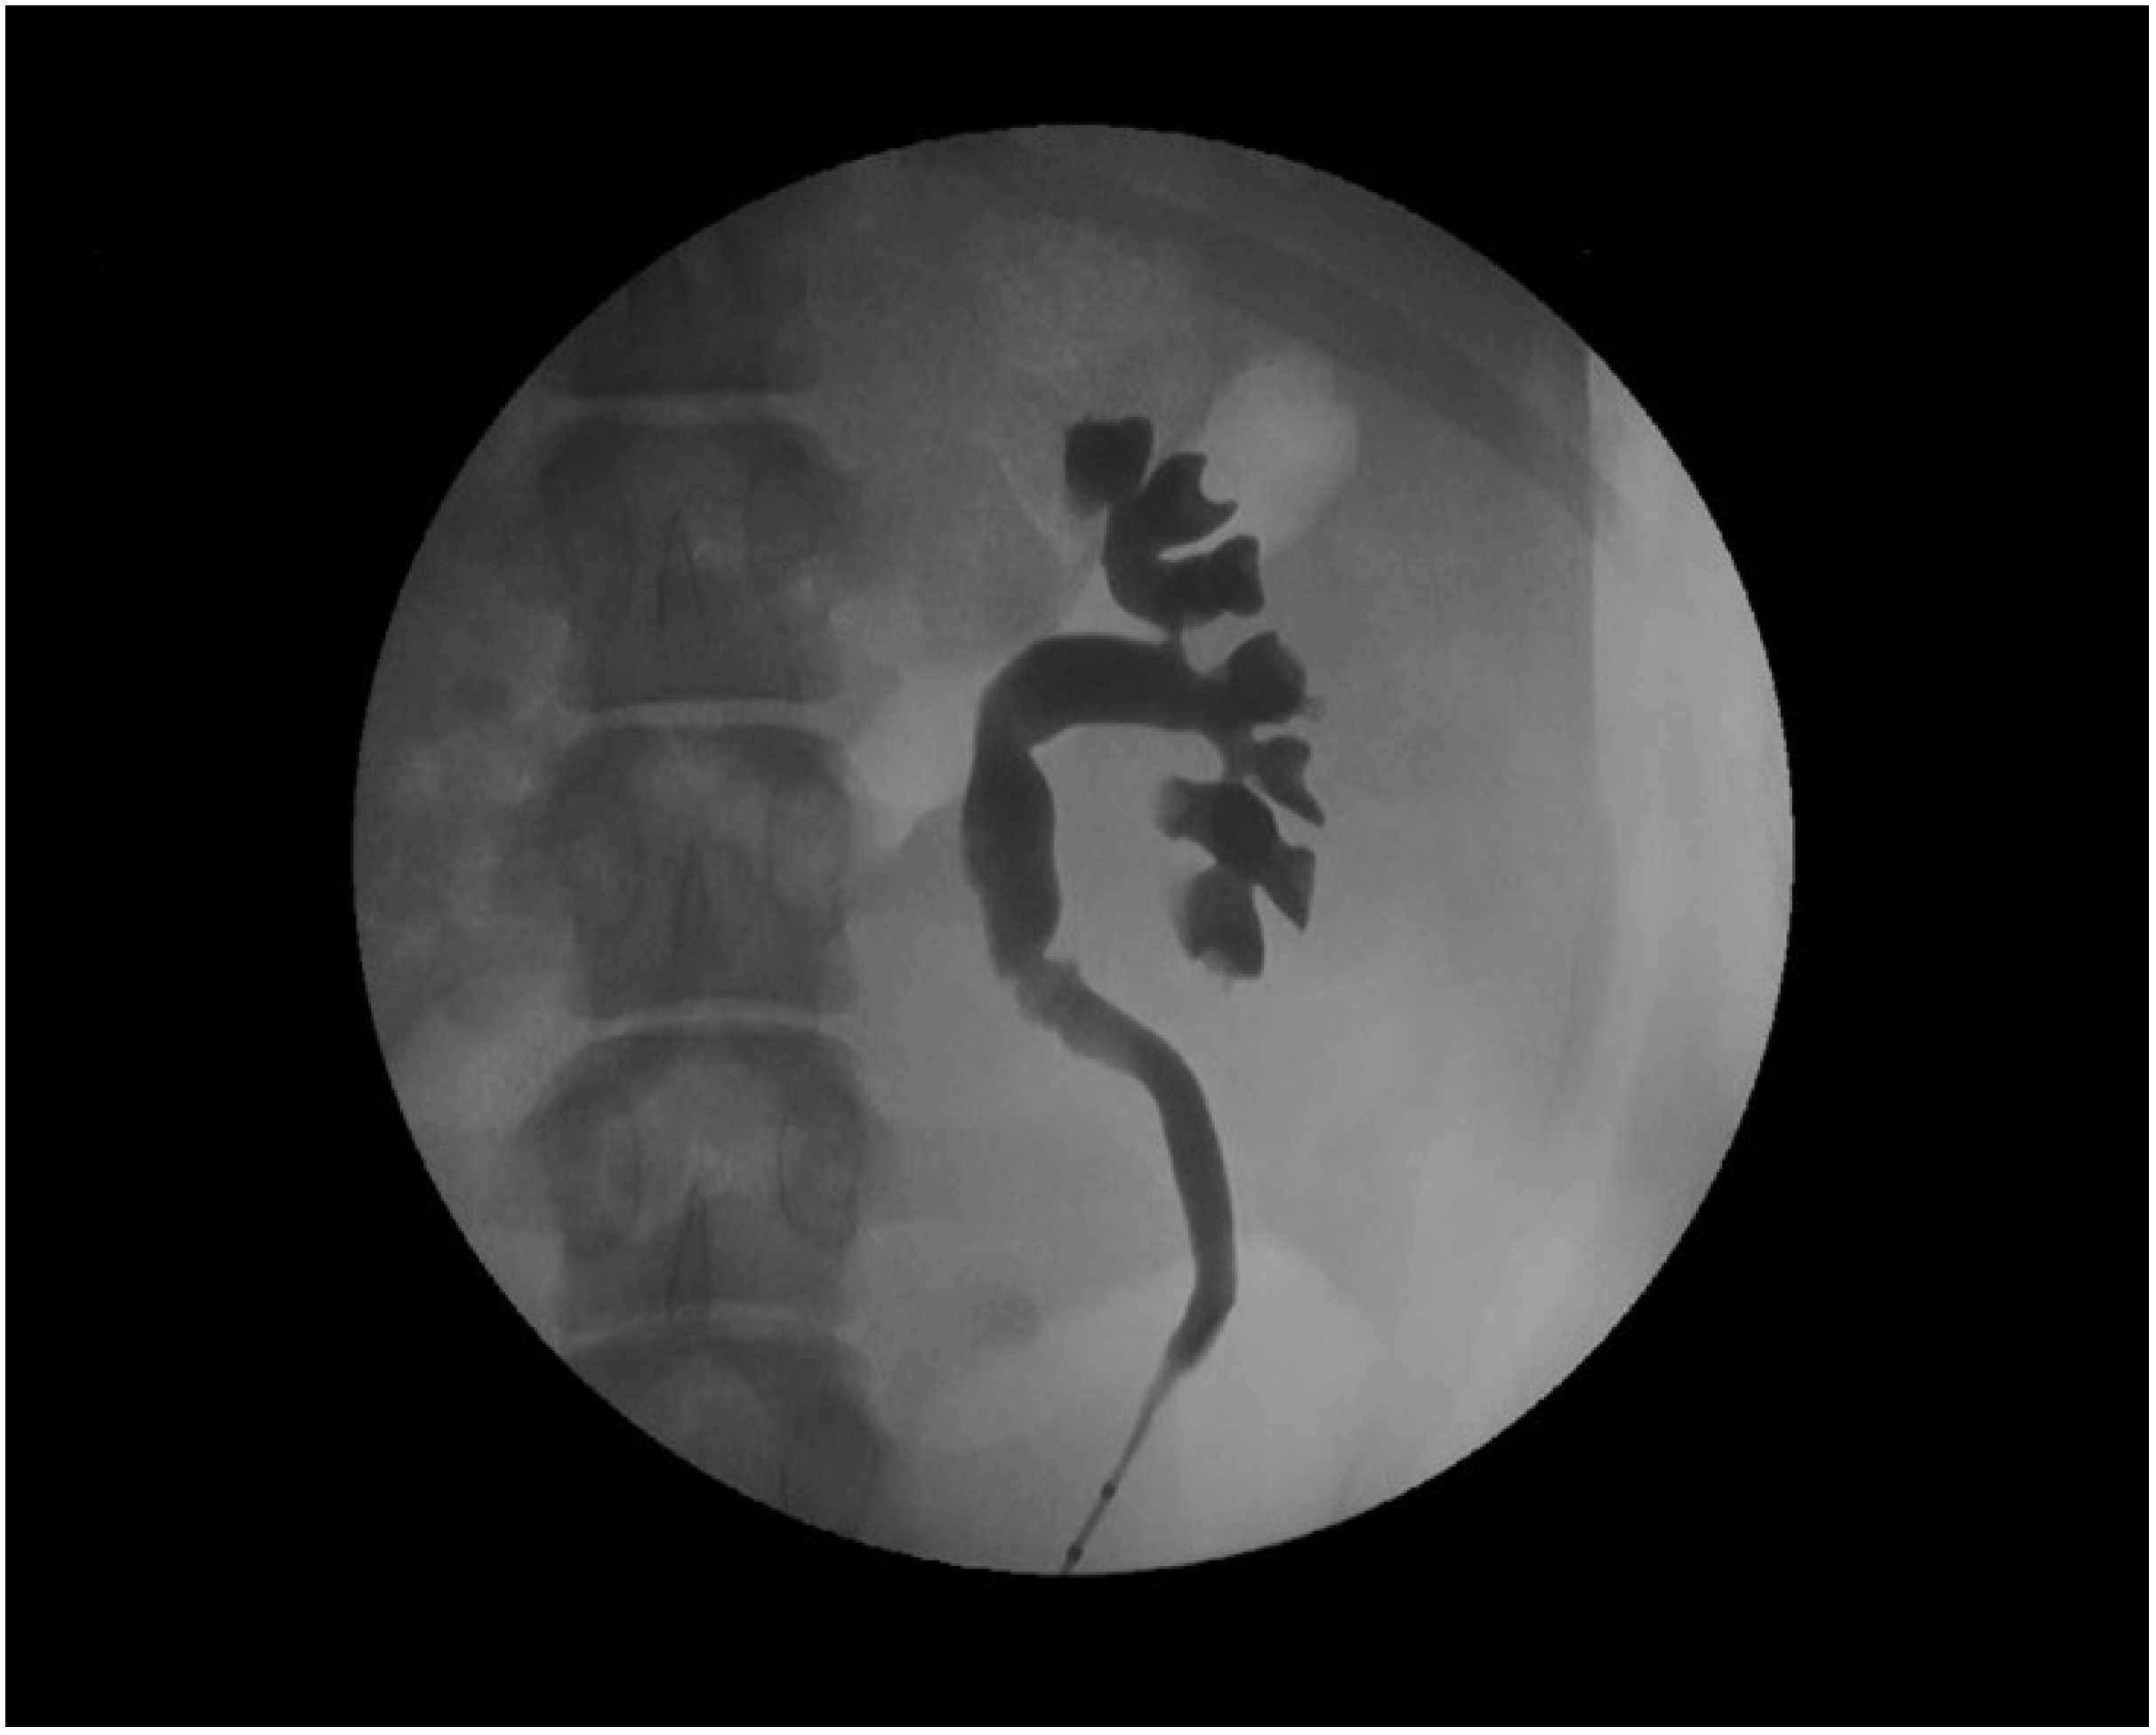

The devices assessed in the porcine model are mainly ureteral stents such as polymeric, antireflux, biodegradable, drug-eluting, and metallic stents [77,78,79,80,81,82]. Usually, stents are inserted retrogradely, although antegrade and cystostomy approaches have been described [77,81,82,83,84,85]. The evaluation of the stent performance in vivo involves blood and urine analysis, urine culture, and imaging tests that include the ultrasonographic assessment of the degree of hydronephrosis [86]. Other radiologic tests such as excretory urography and retrograde ureteropyelography can provide valuable information on urinary patency, stent migration, radiopacity and mode of degradation of biodegradable devices (Figure 4) [65,86,87].

Figure 4.

Retrograde ureteropyelography of a porcine left nephroureteral unit.